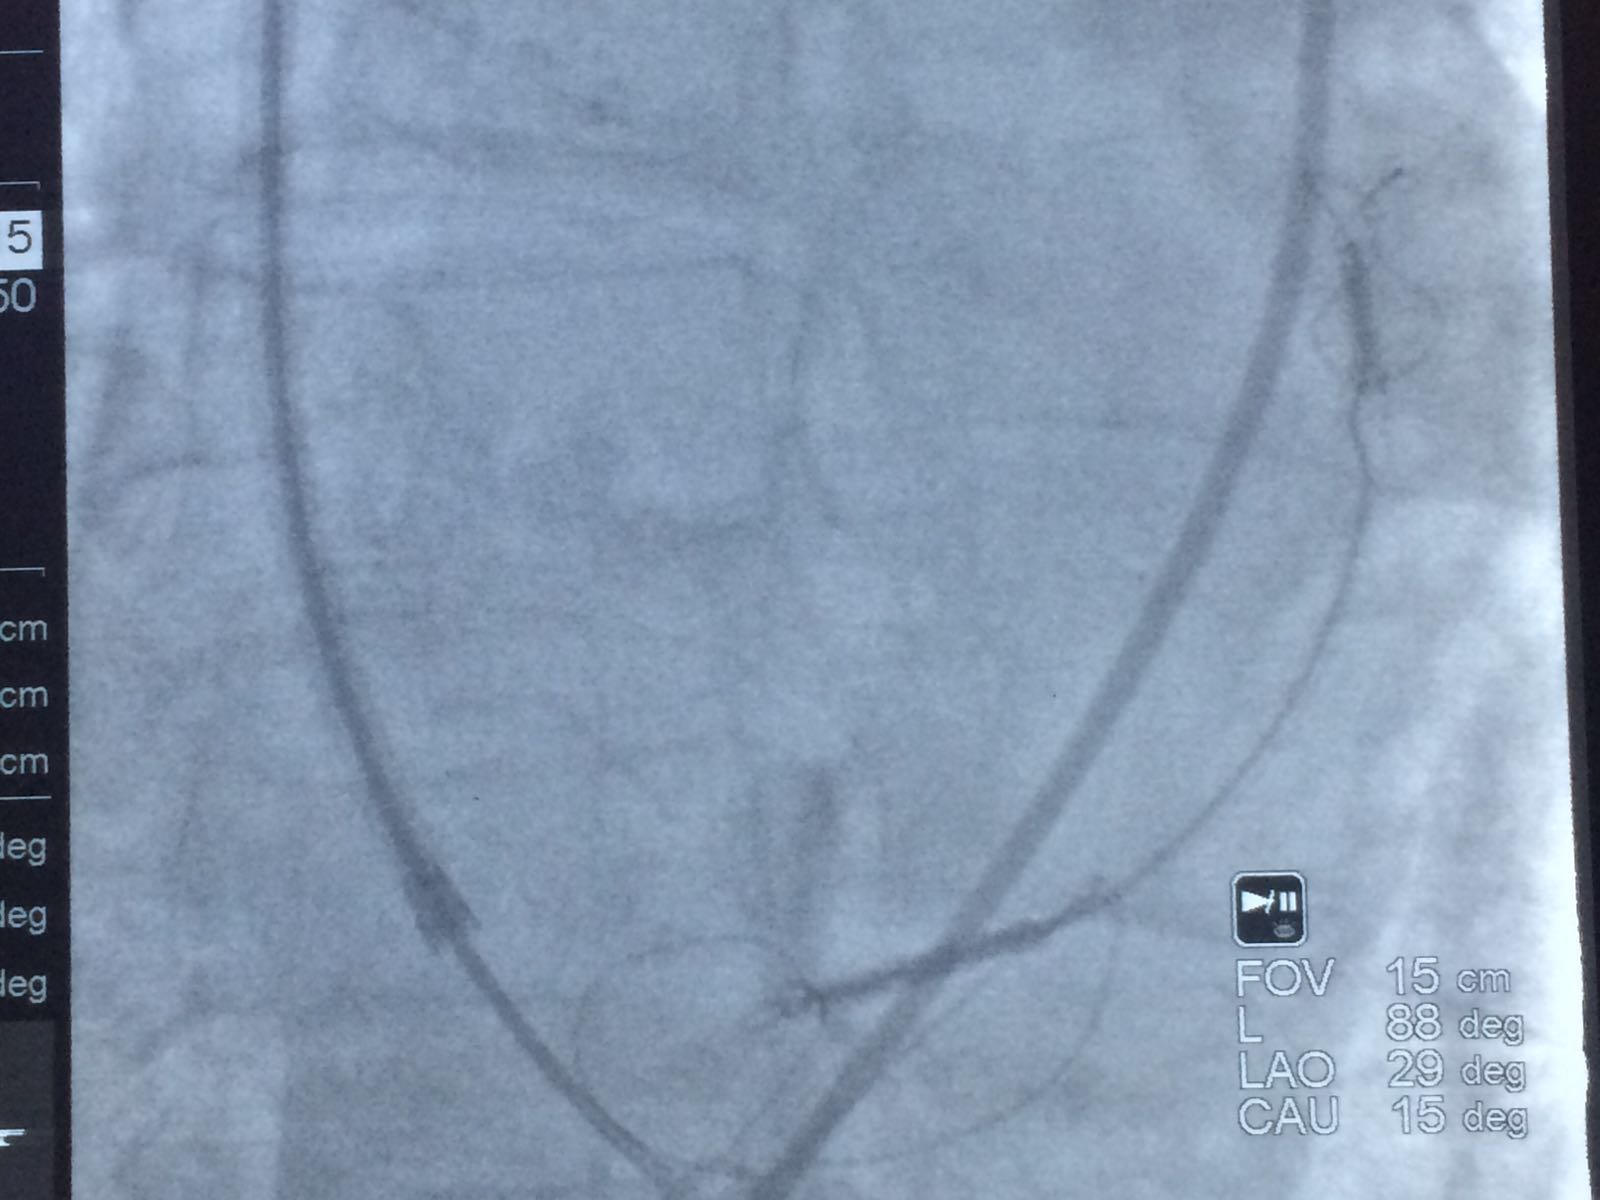

Foto e Video